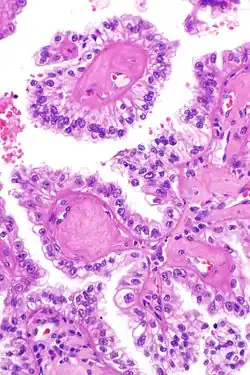

Micrograph showing the characteristic hyalinized papillary cores found in some hereditary leiomyomatosis and renal cell carcinoma syndrome-associated renal cell carcinomas. H&E stain.

The renal cell carcinoma tends to be of the papillary (type 2) form and tends to occur more commonly in women than men with this syndrome. These cancers present earlier than is usual for renal cell carcinomas (typically in the twenties and thirties) and tend to be at relatively advanced stages at presentation. Tumours have rarely been reported in children. These tumours occur in ~20% of those with this mutation suggesting that other factors are involved in the pathogenesis.

The renal cell carcinomas have prominent eosinophilic nucleoli surrounded by a clear halo.